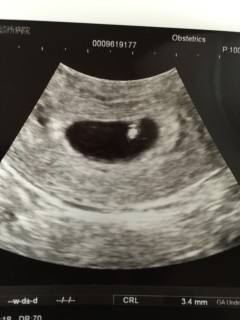

初診が6w0dでした! 赤ちゃんが見え隠れして先生が、頑張って心拍をひらってくれました。 「動きたて」とのことで、リズムもまだ不定期でしたが、次の検診まで赤ちゃんの成長を信じて待ちたいと思います! 赤ちゃんは、3.4mmでした。